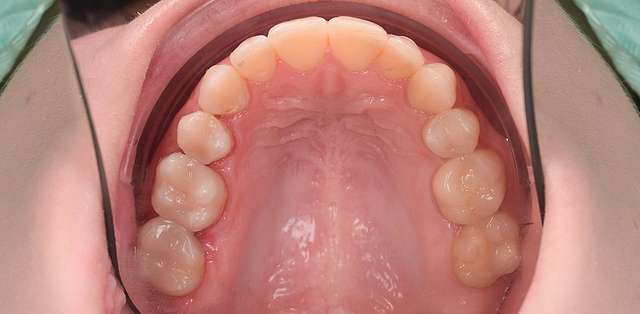

Here we had to deal with a significantly deviated midline, needed to bring one canine on the arch and basically realign teeth on both arches. To finish we did some composite details. When existing teeth have naturally beautiful shapes, orthodontics is many times a superior alternative to prosthetic treatment. It has one disadvantage: requires more time.